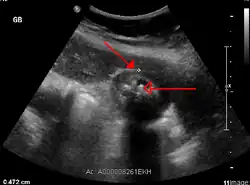

L'échographie hépatique montre une lithiase avec un aspect de cône d'ombre. Il existe un épaississement de la paroi de la vésicule biliaire, qui peut prendre un aspect feuilleté. La sonde d'échographie, passant au niveau de la vésicule, provoque la douleur (on parle donc de « Murphy échographique »). Ces signes sont très sensibles et spécifiques[4]. C'est l'examen fait en première intention.